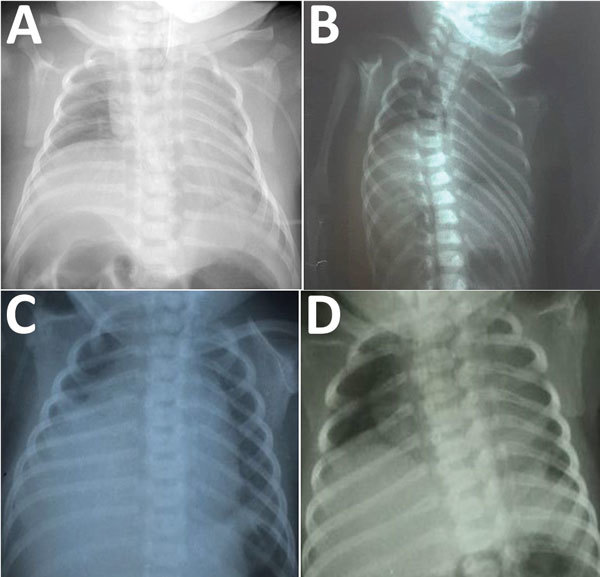

Description:Since the first identification of neonatal microcephaly cases associated with congenital Zika virus infection in Brazil in 2015, a distinctive constellation of clinical features of congenital Zika syndrome has been described. Fetal brain disruption sequence is hypothesized to underlie the devastating effects of the virus on the central nervous system. However, little is known about the effects of congenital Zika virus infection on the peripheral nervous system. We describe a series of 4 cases of right unilateral diaphragmatic paralysis in infants with congenital Zika syndrome suggesting peripheral nervous system involvement and Zika virus as a unique congenital infectious cause of this finding. All the patients described also had arthrogryposis (including talipes equinovarus) and died from complications related to progressive respiratory failure.